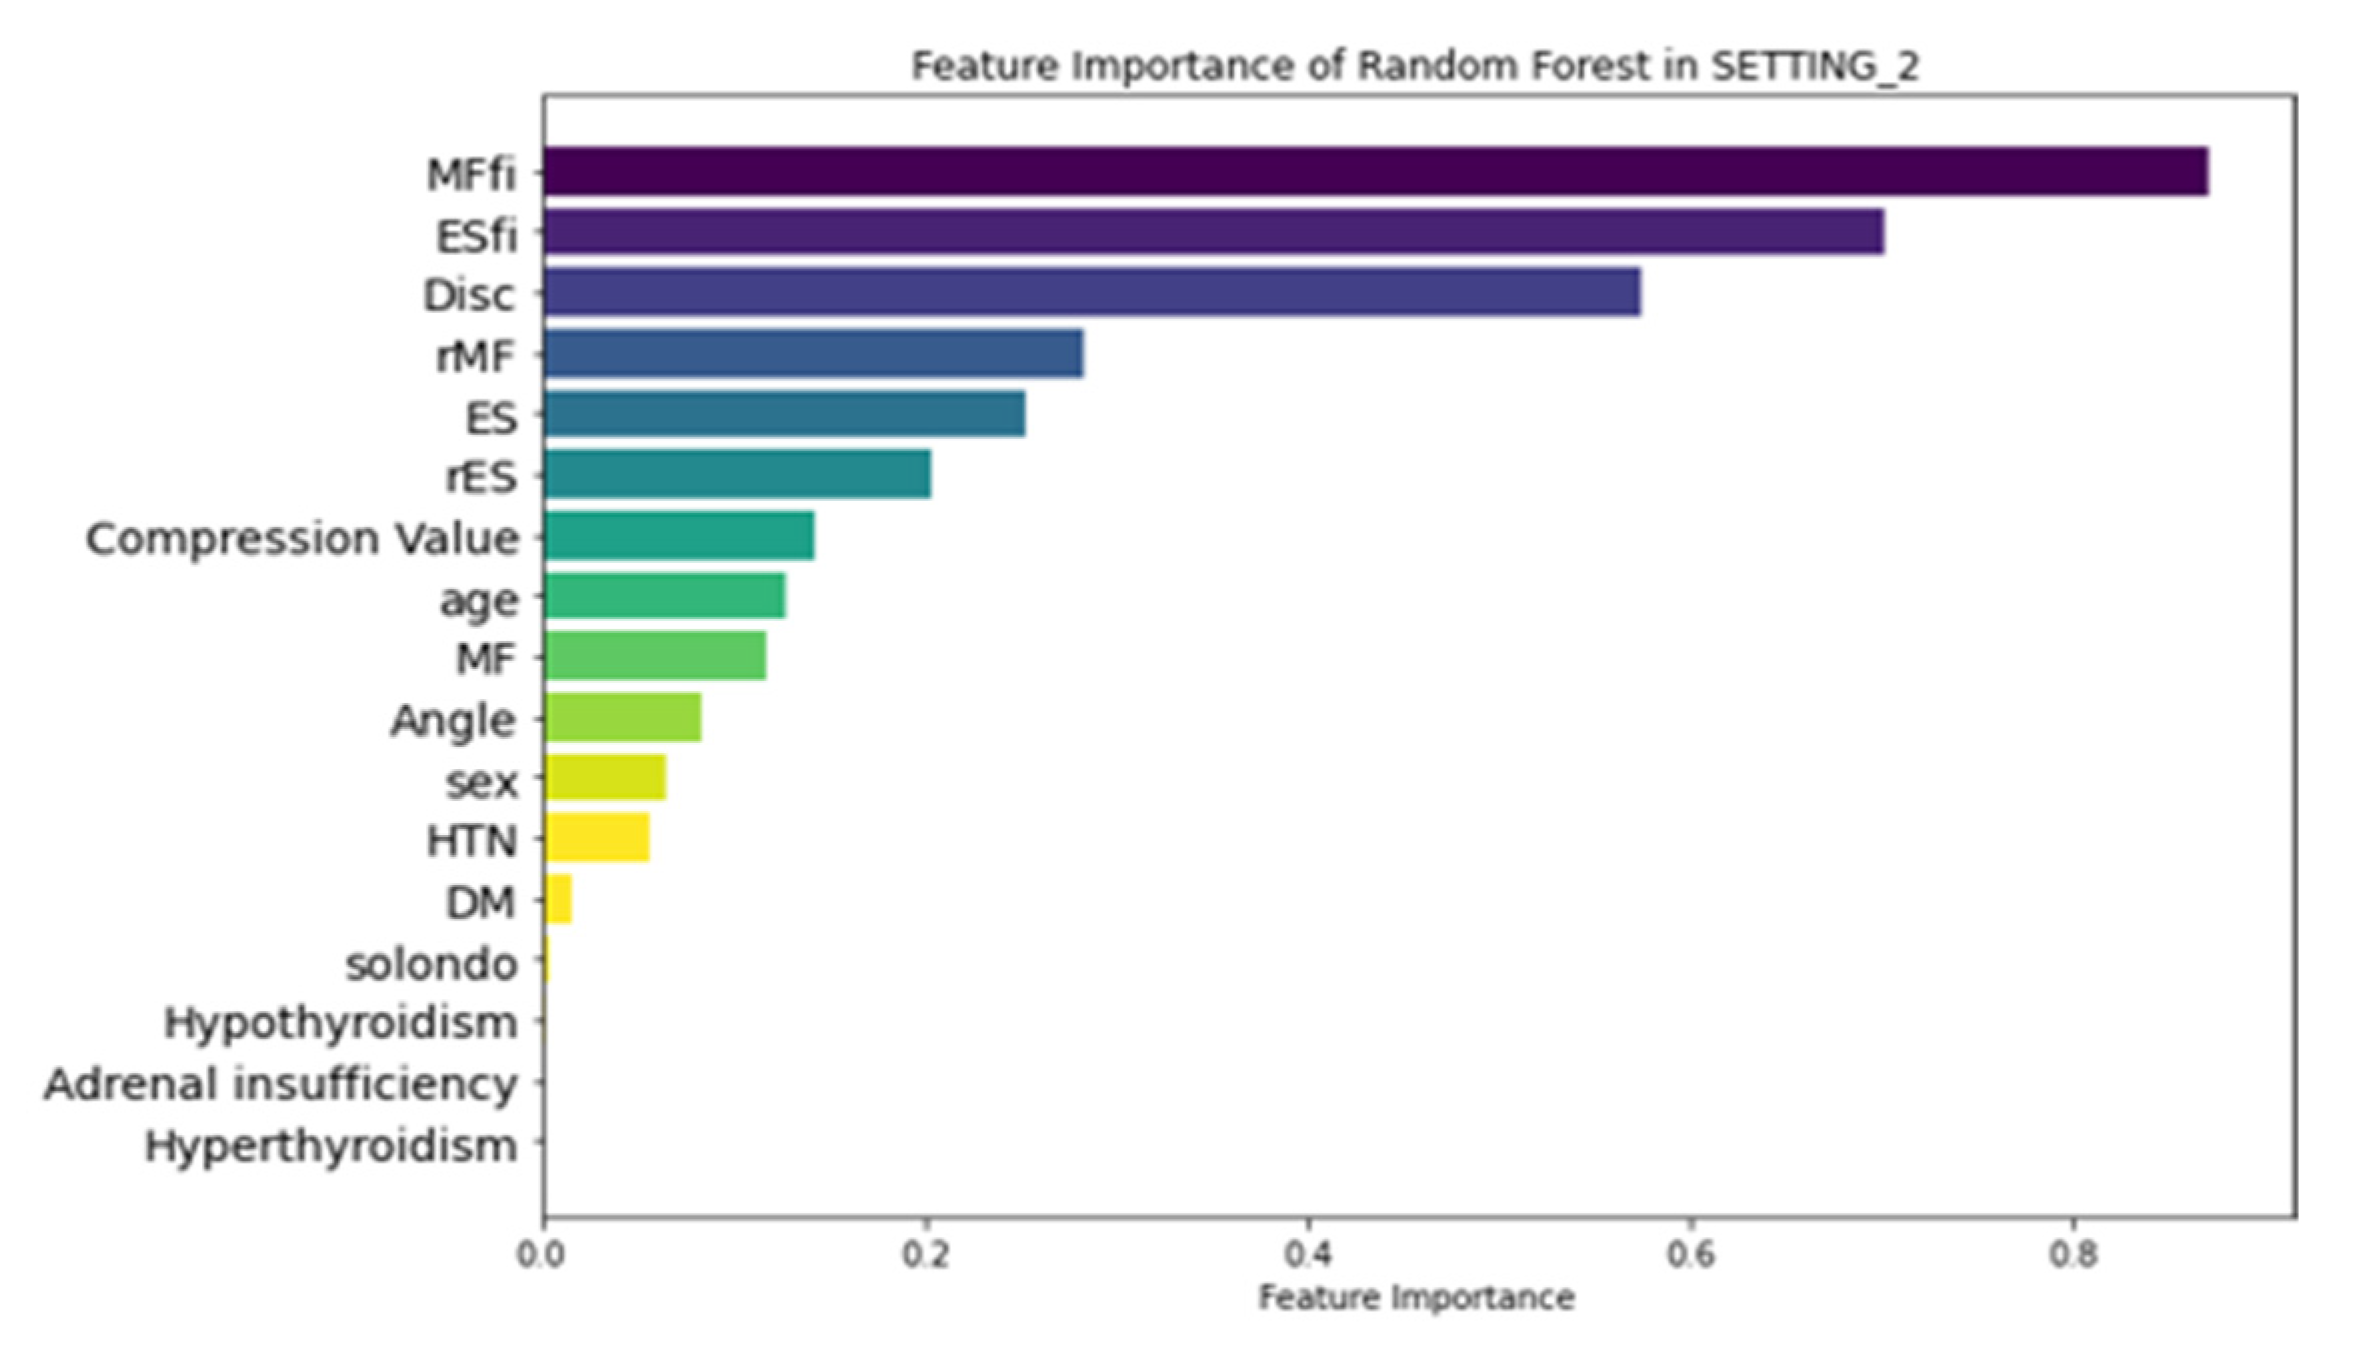

3.3. Feature Importance

| MF | Multifidus |

| ES | Erector spinae |

| MFfi | MF fat infiltration |

| ESfi | ES fat infiltration |

| rMF | Relative CSA of multifidus per CSA of endplate |

| rES | Relative CSA of erector spinae per CSA of endplate |